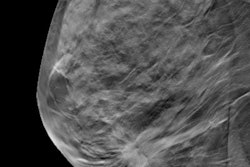

The researchers had sought to make use of AI technology for aiding the challenging task of characterizing breast masses spotted on screening ultrasound exams.

"Considering the small size and less obvious morphologic characteristics of breast masses detected using screening [ultrasound], the quantitative information derived from the [deep learning-based computer-aided diagnosis] software could provide additional details missed by the expert radiologists; furthermore, such information could prove to be substantially useful for the differentiation of breast masses while facilitating patient management in the clinical setting," they wrote.